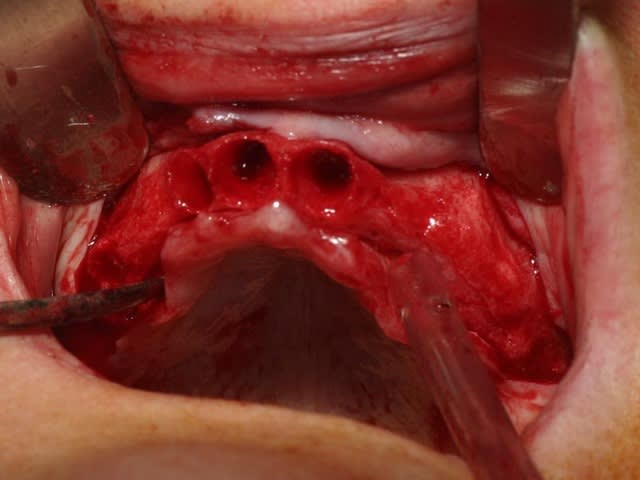

bon, toujours aussi speed je suis, mais après certaines réclamations, et malgrès ma réticence à poser un cas non "consolidé", voici en avant première mon premier all on 4, version photos ratées et non retouchées, mais... speed je suis je vous disais ;)

sto le bla bla, et pasons le diaporama... bon voyage au pays de la mise en charge immédiate totale au maxillaire de fille carole sur dame ginette, une patiente en or que j' adore, et pour qui je suis très très heureuse d' avoir pu réaliser cette chirurgie et la première étape prothétique.....